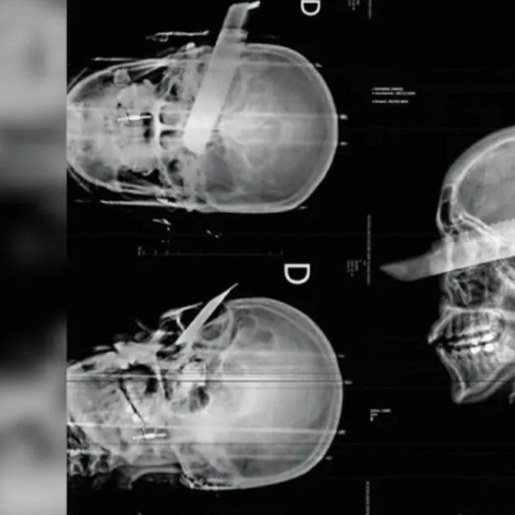

Uma mulher sofreu uma tentativa de feminicídio na manhã desta segunda-feira, 2, em São Carlos, ao ser atacada pelo companheiro dentro da residência do casal. O agressor desferiu um golpe de faca no rosto da vítima, atingindo o olho direito, mas o crime não se consumou, segundo a polícia, graças ao pronto atendimento médico.

Conforme apurado pela Polícia Civil, o suspeito agiu com a intenção de a matar. A vítima conseguiu escapar parcialmente da agressão, mas foi atingida enquanto tentava fugir. Ela recebeu atendimento de emergência e passa por acompanhamento médico.